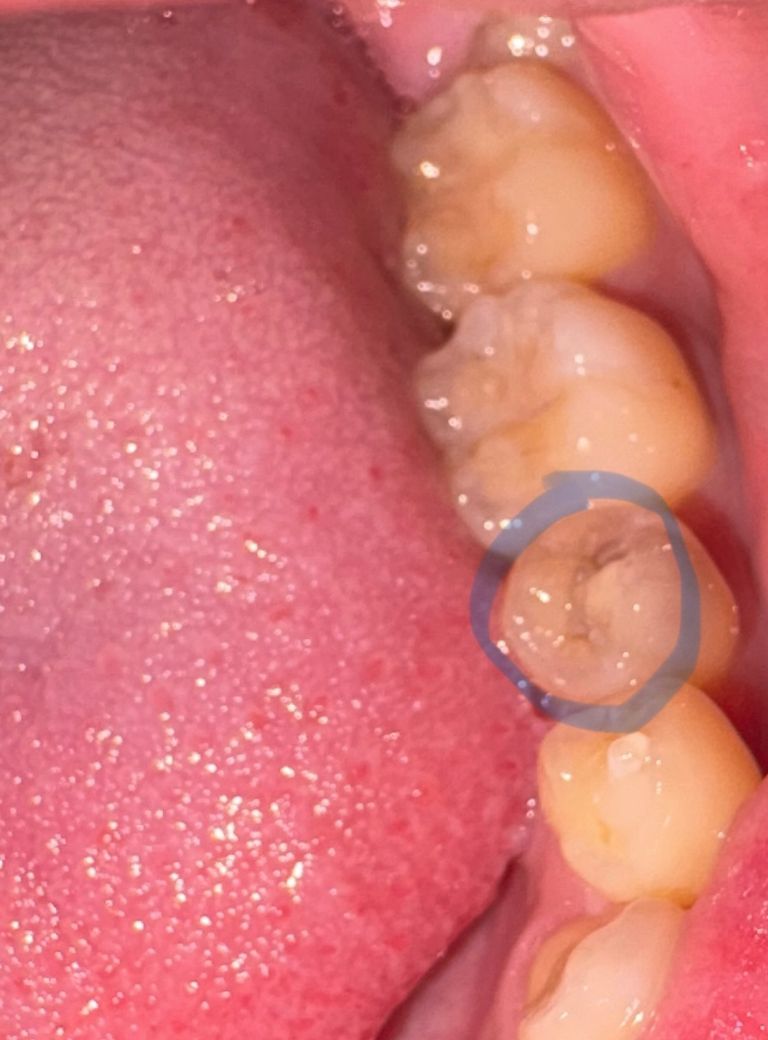

충치인지 레진 깨짐인지 여부가 궁금합니다.

오늘아침 일어나서 찬물을 마셨는데 사진 속 이가 매우 시렸고, 손으로 긁거나 뾰족한 물체로 톡톡 건드려보면 다른 이에 비해 감각이 크게 느껴집니다.

충치인지 레진 재치료가 필요한 것인지 육안으로 식별이 잘 안 돼서 궁금하여 질문 남깁니다.

사진에 보이는건 레진치료를 한건 아니고 충치가 잇는거 같으니 치과에 가셔서 체크를 받아보시는게 좋을것같습니다.

사진 해상도가 흐리지만 색깔이 검은 것으로 보아 충치인 것으로 보입니다. 치과에 가서 치료해야 할 것으로 보입니다.

사진으로 봤을 경우에는 치아의 하방에 충치가 큰것으로 보입니다. 인접면 충치가 내부로 커졌을 가능성이 높습니다.

방사선 사진을 찍어봐야 명확히 알 수 있겠지만 치아의 색으로 보아 치아 겉은 멀쩡해보이지만 안쪽이 많이 썩은 것으로 보입니다.

찬물에 심한 통증이 느껴지는 경우 보통 비가역적 치수염으로 번진 경우가 대부분이라 아무래도 신경치료와 크라운 치료가 필요할 것으로 보입니다만 빠른시일내에 치과에 내원하셔서 검사를 받아보시길 바라겠습니다.

치과가셔서 엑스레이를 찍어보는 것이 좋겠습니다 하방 이차우식의 가능성도 있어보입니다